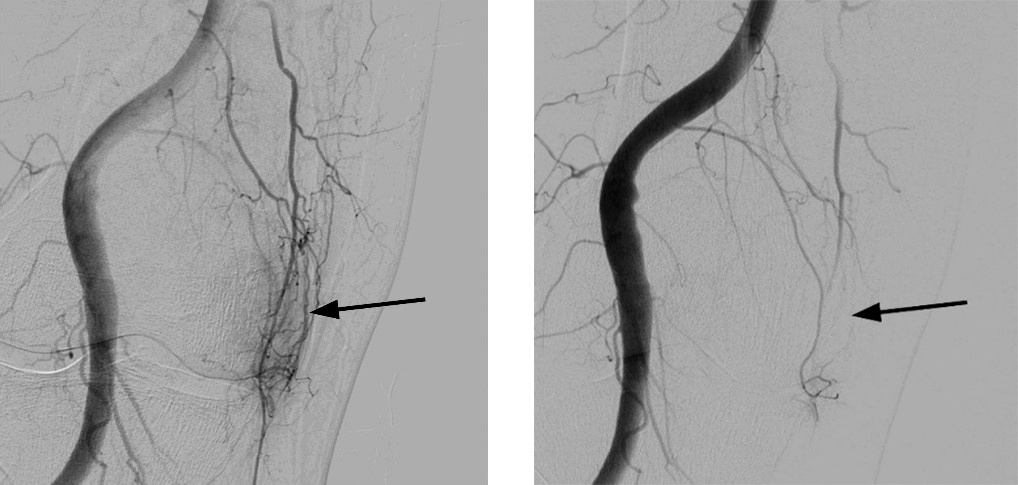

Mikro-Embolisation: Identifikation abnormer Gefässe auf der Innenseite des Kniegelenks (Pfeil linkes Bild), welche nach Einbringen des Medikaments (Embolisation) nicht mehr nachweisbar sind (Pfeil rechtes Bild).